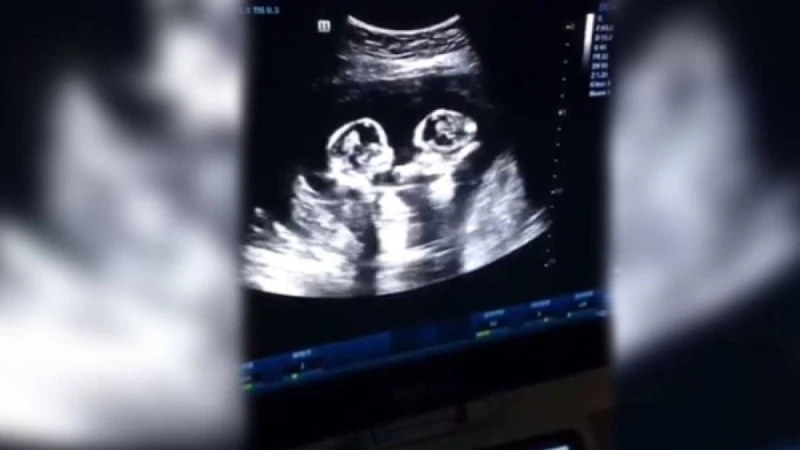

Құрсақта жатқан егіздер "төбелесті" - видео

НҰР-СҰЛТАН, 21 сәуір - Sputnik. Қытайда ультра дыбыстық зерттеу кезінде ата-ана жүктіліктің төртінші айында құрсақтағы балаларының өзара қарым-қатынасына куә болды, деп хабарлайды Daily Mail.

Ультра дыбыстық зерттеуді егіз апалы-сіңлінің әкесі видеоға түсіріп алған.

Роликтің кадрларына қарағанда, қыздар анасының ішінде төбелесіп жатқан сияқты. Мұны қызық көрген 28 жастағы болашақ әке видеоны Желіде жарияласа керек. Бейнежазба тез тарап, 2,5 миллион лайк және 80 мың пікір жинады.

Егіздерде амниотикалық қап пен жолдасы ортақ болған. Бұл - өте сирек кездесетін құбылыс әрі жүктіліктің аса қауіпті түрі: мұндай жағдайда балалардың 50 проценті ғана аман қалады.

Басылым атап өткендей, егіздер кесар тілігі арқылы аман-есен дүниеге келіпті.